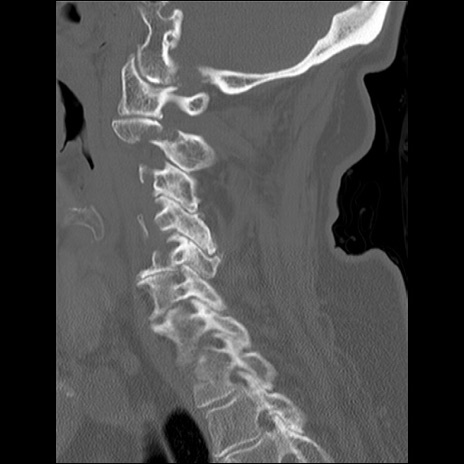

症例48 頚椎CT(矢状断像)

頚椎CT